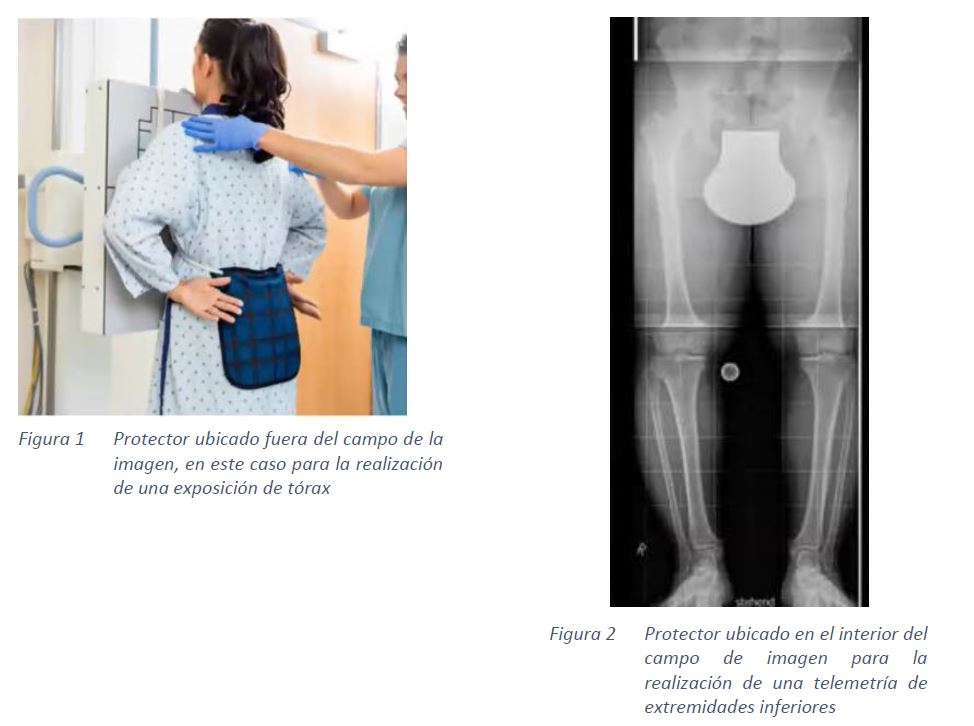

La ubicación de los protectores en los pacientes puede ser:

- Fuera del campo de imagen

- En el campo de imagen